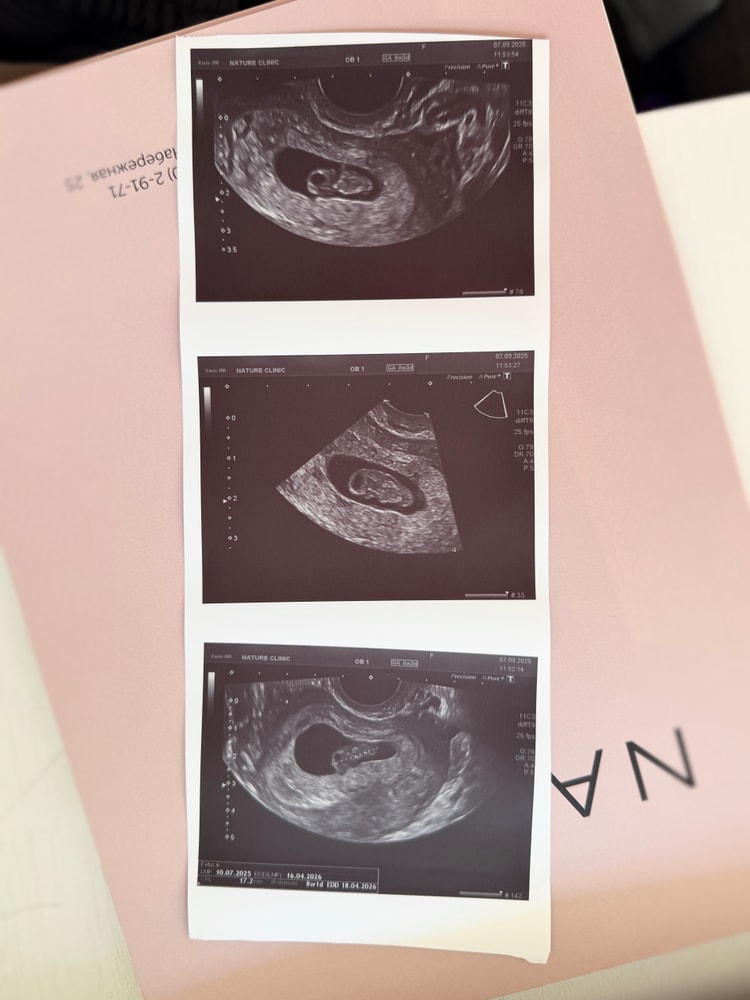

Пошла 9 неделя👼🏻

УЗИ, КТГ, доплерСегодня на узи поставили точный срок 8+1 (О была поздняя, по М примерно 8+4)

Малыш уверенно догоняет свой срок, ну и собственно первые фото этой креветочки - пока еще с хвостиком, но уже видно зачатки ножек и ручек😁

КТР - 17 мм, СБ - 164 уд/мин😌

Было 12 дней назад - 5 мм, 154 уд/мин